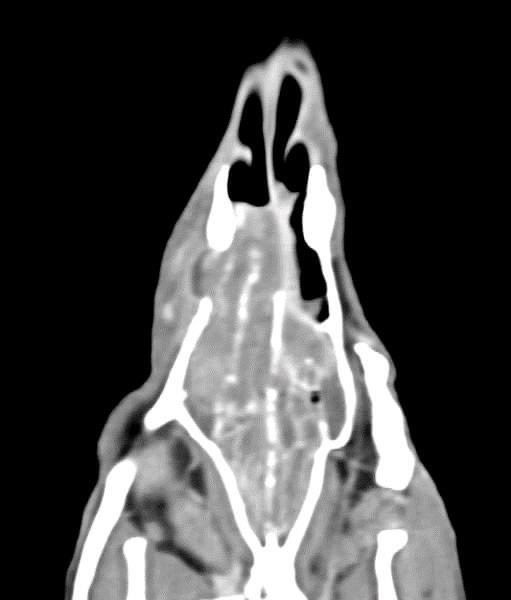

狗狗 鼻腔腫瘤 淋巴癌

鼻腔腫瘤的診斷需要仰賴電腦斷層掃瞄定位病灶處,同時使用鼻腔內視鏡探查、採樣才能確診,同時有這兩項設備的醫院並不多,所以臨床事並不是那麼容易確診。

狗狗如果有打噴嚏、鼻分泌物 鼻塞,對藥物治療反應不好, 就還是要做進一步檢查才會比較安心唷!